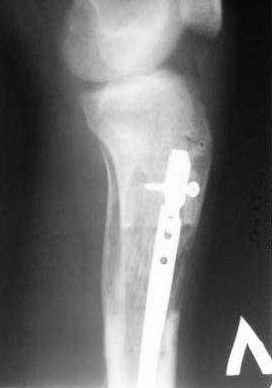

Пациент 19 лет, производственная травма, придавлен тяжелой плитой. Политравма (ISS 21).

1 - рентгенограмма (прошу прощения за качество) при поступлении;

Произведено ПХО, acute shortening (5 см), фиксация стержневым аппаратом Hoffman.

3,4 - через 4 недели наложен спице-стержневой аппарат, произведена остеотомия большеберцовой кости в верхней трети, раны зажили, проводилась дистракция в аппарате.

5, 6 - через 2,5 мес после травмы выполнен закрытый остеосинтез блокируемым штифтом.

7, 8, 9, 10, 11 - через 8 мес после травмы перелом сросся.